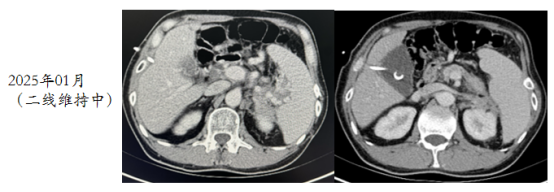

image.png

图5 二线C3后复查CT结果

(2024年09月)C6后复查CT评效:结肠脾曲管壁增厚同前,肝多发低密度影,同前。胰腺区,左肾前,脾内侧多发转移同前。评效维持PR。开始BEV+CAPE维持治疗。

图6 二线C6后复查CT结果

(2025年01月)复查CT评效:结肠脾曲管壁增厚稍减轻,肝多发低密度影同前。胰腺区,左肾前,脾内侧多发转移同前。评效维持PR。继续BEV+CAPE维持治疗。

图7 2025年1月复查CT结果